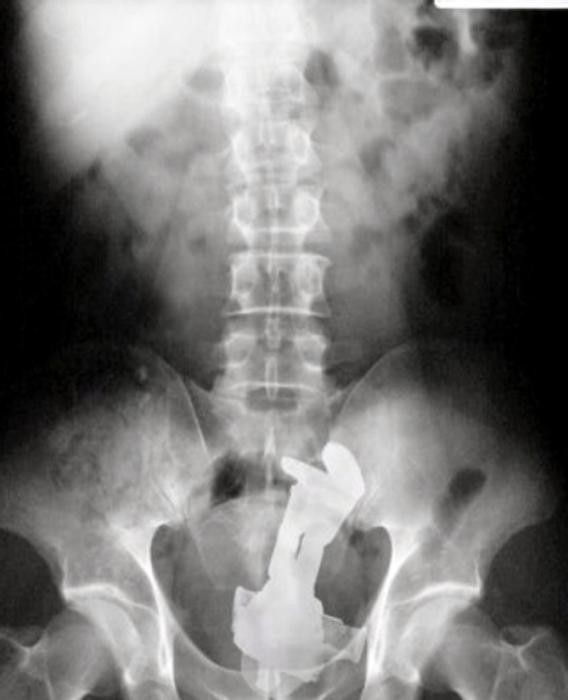

33 radiographies qui prouvent que les gens font des choses douteuses avec leur corps !